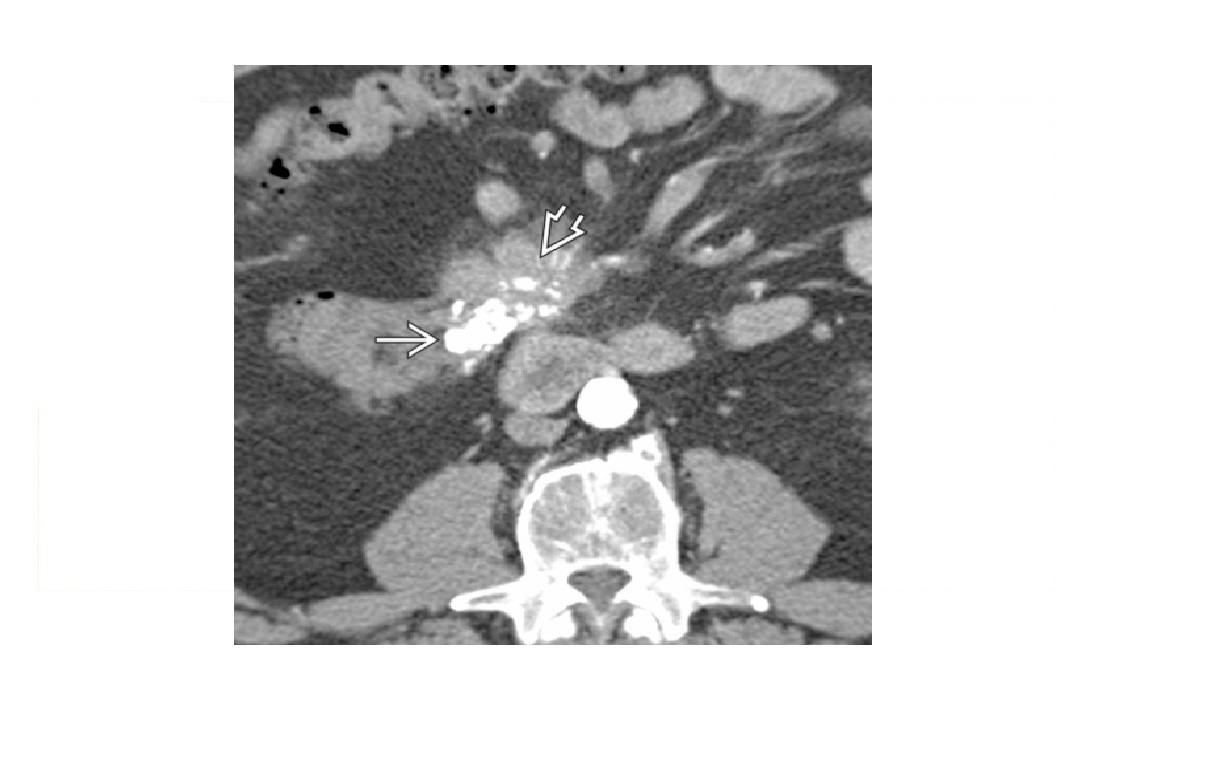

Carcinoid

spiculated mesenteric mass with calcification/ desmoplastic reaction

Tethering of SB loops

90% arise in terminal ileum/appendix

Hyper-vascular liver mets - Carcinoid syndrome

111I- Octreotide scans (1st - highest sensitivity)

or 123I-MIBG (for 10% dont take up octreotide)

for Dx and staging

Big centres use gallium PET

Assocaited with MEN 1 or MEN 2a

DDX

Sclerosing mesenteritis/ mesenteric pannicultuis

- FAT HALO sign - Mass envelop vessels, but preservation of fat around vessels

- usually jejunal small bowel mesentery

Gastrointestinal Stromal Tumor (GIST)

- Hypervascular tumor, not associated with desmoplastic effect on mesentery

Small Bowel Carcinoma

- More common in duodenum or jejunum than in ileum

- Causes luminal obstruction

- Mass and metastases are hypovascular